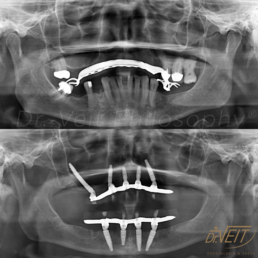

Arte de reabilitar os casos “impossíveis”. Pacientes que buscam a reabilitação oral podem conquistar um belo sorriso com segurança, mais conforto e tranquilidade com o uso do Implante Zigomático. A técnica possui o diferencial de realizar a implantação no osso zigomático e é indicada para casos de perda óssea maxilar avançada.